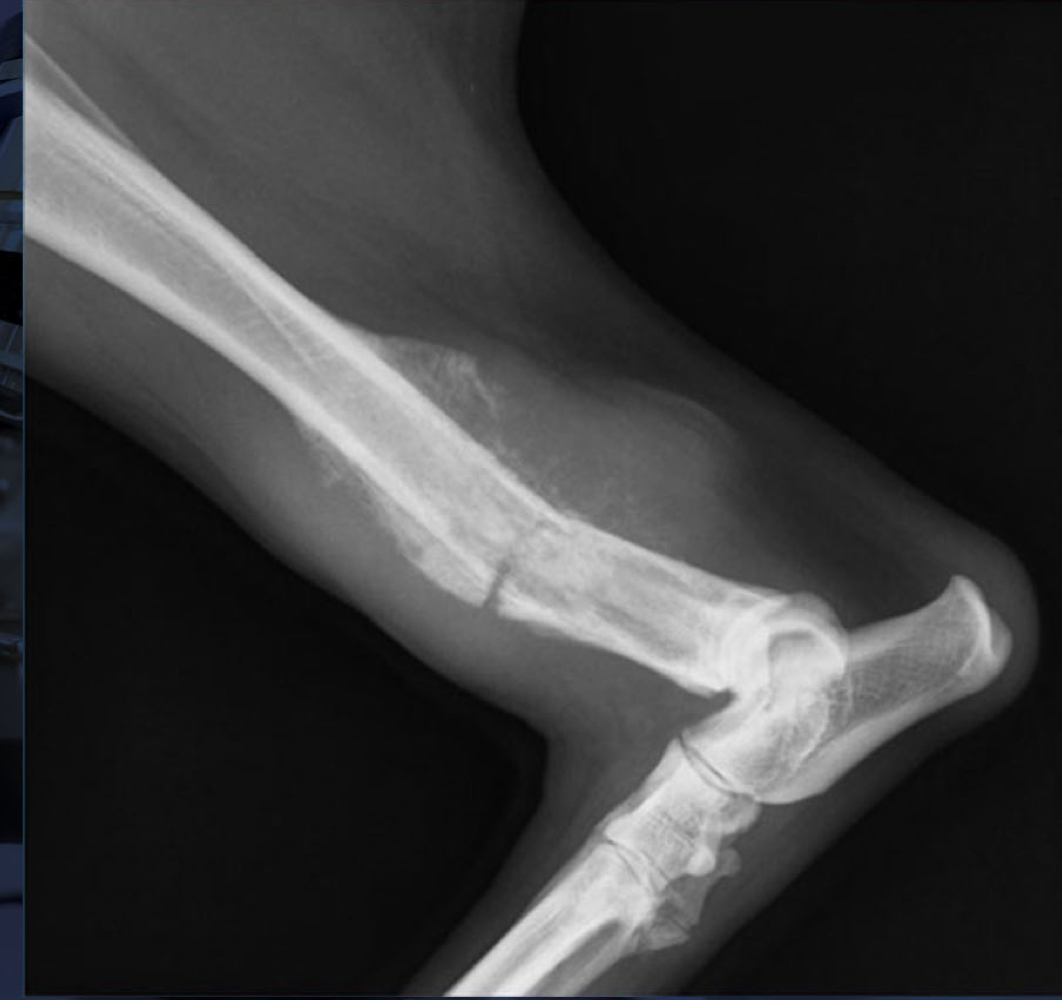

Avulsion fracture:

A

cartilaginous tibial tuberosity